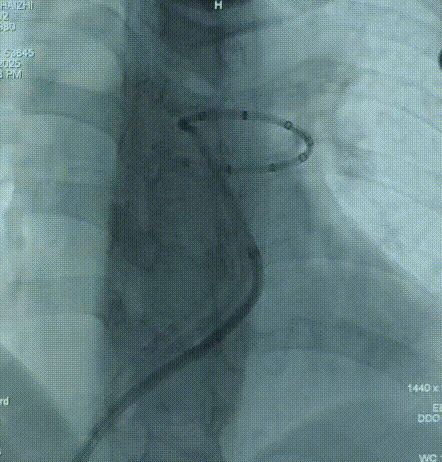

二次消融位置

PADN术消融黄金三靶点